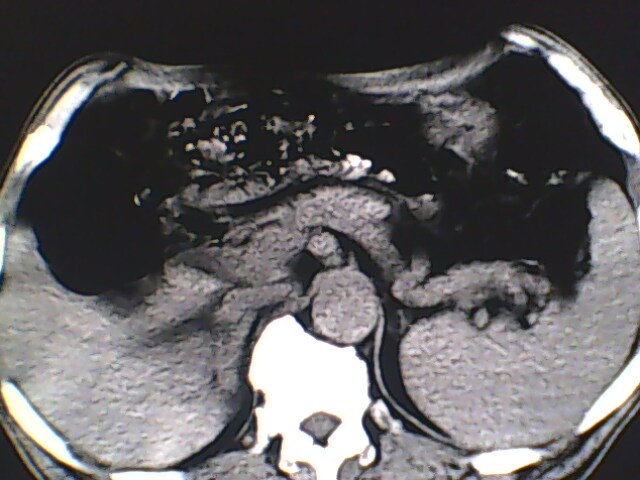

男,56岁,高血压,临床怀疑肾上腺问题,肝脏怎么那么高啊?能描述一下么?

右侧膈膨升,间位结肠,胸腰椎退行性骨关节病,右侧肾上腺可疑增生(图像颗粒太粗,窗太窄,不好看)。

支持 右侧膈膨升,间位结肠;胸腰椎退行性骨关节病;双侧肾上腺可疑增生。